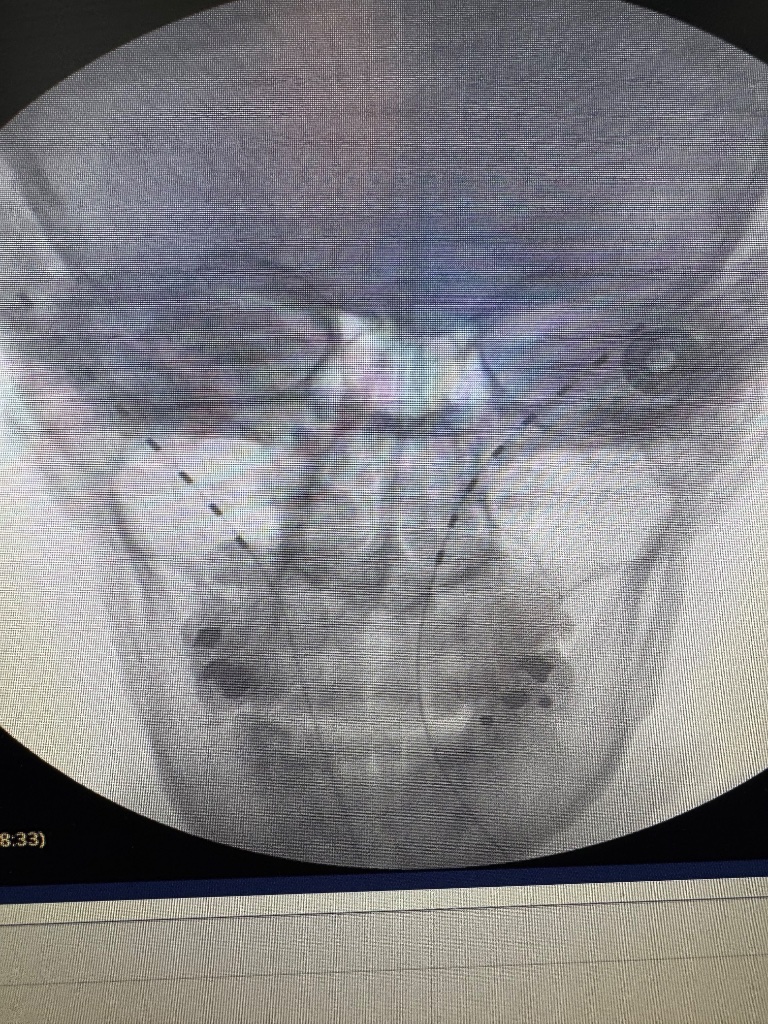

I have been migrating to the C2 DRG PNS approach for posterior scalp neuralgias. Satisfied patients. Less mechanical wear/tear as you aren't crossing the C0/C1/C2 movement axis and much lower risk of erosion with the depth in the scalp. External pulse generator on the chest or shoulder depending on patient preference

FYI, I found the pictures in the paper from Stanford quite interesting.

Can you link the paper? Where is the tip even? Is that in the canal? No complications?

I usually place a Sprint lead just superior to the C2-3 facet line. Have had some slam dunks, and some so so results. High reward:risk ratio. Might start giving the C2 DRG approach a shot though.

I did one of these recently after the patient had tried, ESIs, C2-4 CRFA, GONB, PT, neck brace, meds, etc. Similar placement to the article with a shallower entry and dipped down to final target. Pt isn't a surgical candidate, older gentlemen, with kyphosis. He did excellent, during the trial, just implated, post op upcoming. I'll keep you posted.